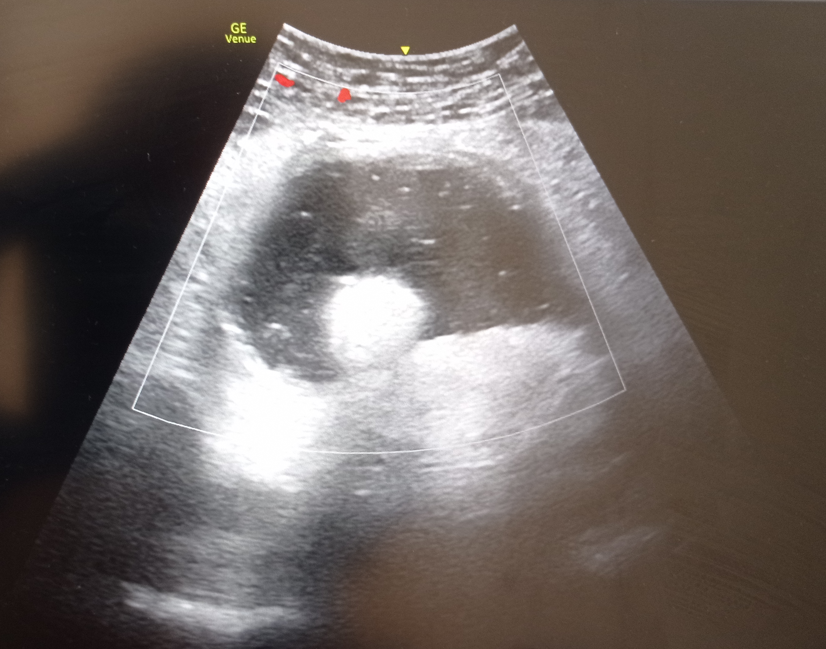

En urgencias, administramos analgesia de primer escalón. Tras 3 h de evolución, se decide realizar ecografía abdominal a pie de cama por persistencia del dolor viendo una imagen sugestiva de masa adyacente a ovario derecho que no conseguimos visualizar.

Tras realización de TAC abdominopélvico describen teratoma torsionado de ovario derecho.

Teratoma torsionado de ovario derecho.

La ecografía clínica en este caso, ayudó a buscar el origen del dolor en un abdomen agudo tras identificar una exploración ecográfica abdominal anormal y necesidad de ampliar el estudio.